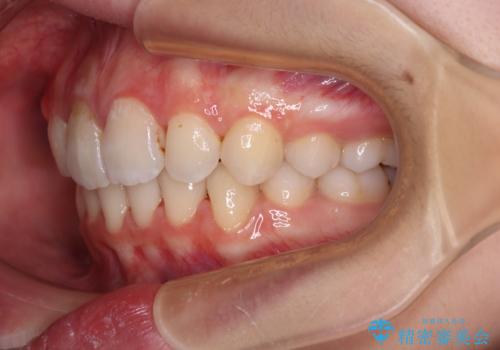

高校生ということもあり、治療期間は2年を切るスピードでした。

舌の突出癖は十分に改善されたとは言えない状態でしたので、今後の後戻り防止対策として、経過観察中も舌のトレーニング指導を行っていくこととなります。